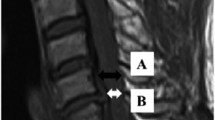

In all available follow-up examinations, tract-specific signal change was evaluated without any clinical information. First, the level of the injury was determined on sagittal T2w. Evaluation of the axial T2w consisted of evaluation for (1) T2w hyperintense signal change in the region of the dorsal column (DC) one level above the level of the injury, (2) T2w hyperintense signal change in the region of the lateral corticospinal tract (CS) one level below the level of the injury, and (3) T2w hyperintense change in the region of the lateral spinothalamic tract (ST) one above the level of the injury. Signal abnormality was read as present or absent. Examples for signal abnormality in each tract are shown in Fig. 2.

Sagittal and axial T2w MRI of the cervical spine of five different patients demonstrating examples of signal intensity change consistent with Wallerian degeneration (WD) in the dorsal column (DC), the lateral corticospinal tract (CS), and the lateral spinothalamic tract (ST). Axial plane is indicated by the blue line on the corresponding sagittal image. a A 19-year-old patient 348 days after motor vehicle accident (MVA) demonstrating WD in the DC on axial images (white arrow). On median, sagittal imaging, WD (white arrows) can be appreciated from the injury upwards to the medulla oblongata. b A 22-year-old patient 109 days after fall demonstrates WD in the DC on axial and median sagittal imaging (white arrows). In the anterior cord, bilateral WD in the ST is seen (black arrowheads). c A 60-year-old patient 111 days after surfing accident also demonstrates WD in the DC (white arrow) and ST (black arrowheads) on axial imaging. On median sagittal imaging, faint WD in the DC is seen (white arrows). d A 50-year-old patient 323 days after MVA demonstrates WD in the CS (white arrows) on axial imaging. On paramedian sagittal imaging, faint WD in the CS from the injury downwards can be appreciated (white arrows). e A 55-year-old patient 216 days after fall demonstrates WD in the CS on axial and paramedian sagittal imaging (white arrows)